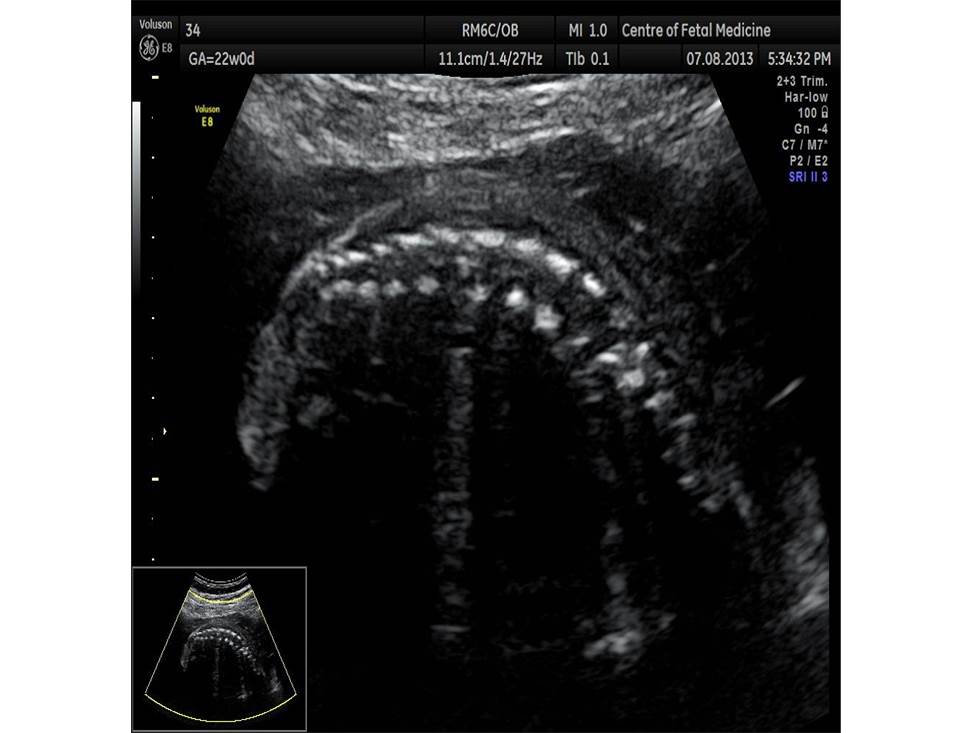

Вопрос 5

Проанализируйте изображения плода в 22 недели и установите диагноз